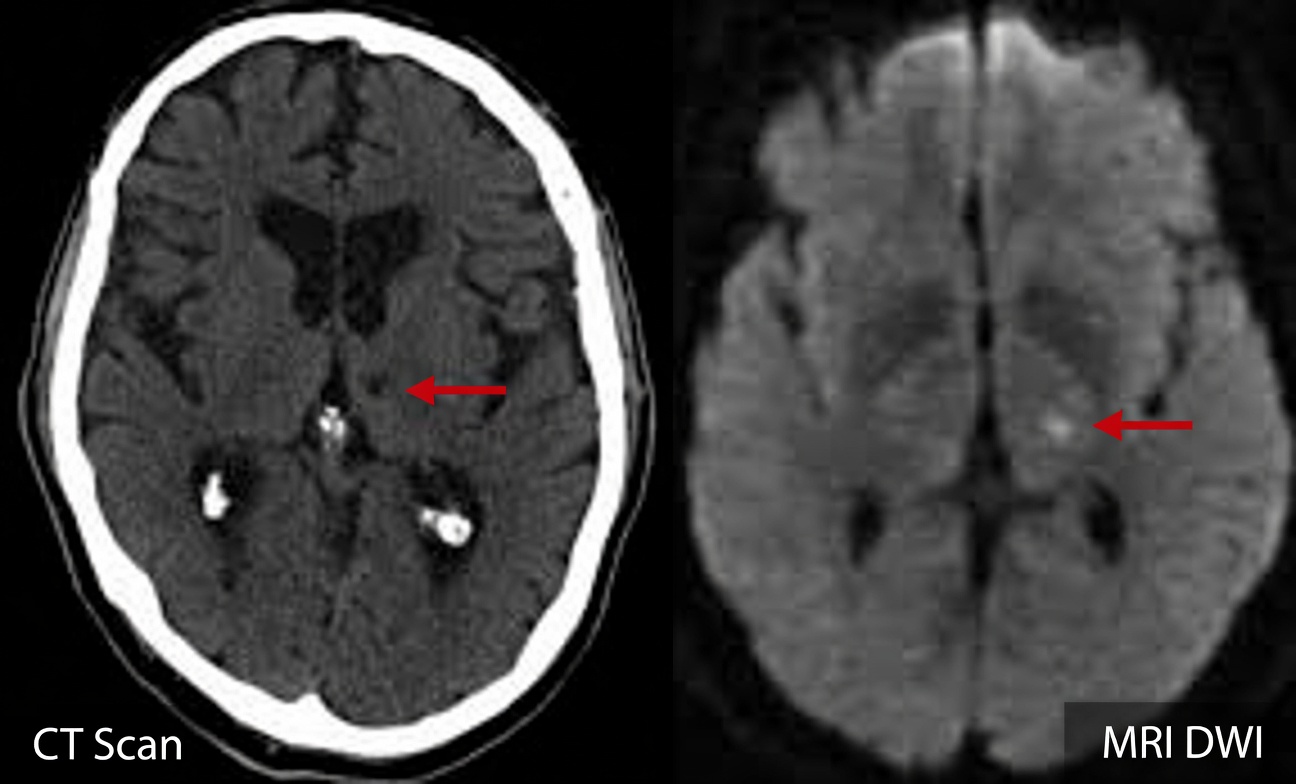

Why Lacunar Stroke Warning Signs Are So Easy to Miss

Lacunar stroke warning signs develop when tiny, deep blood vessels in the brain become blocked. This can create small cavities (lacunes) in critical regions such as the basal ganglia and thalamus. Many older adults live with these changes for years, noticing their balance, focus, or energy slowly slipping while assuming it’s all part of aging.